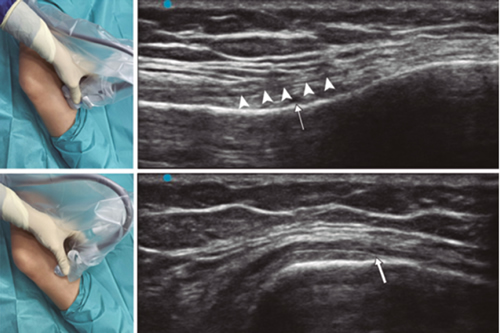

Figure 2

Figure 3

Figure 4

Figure 5